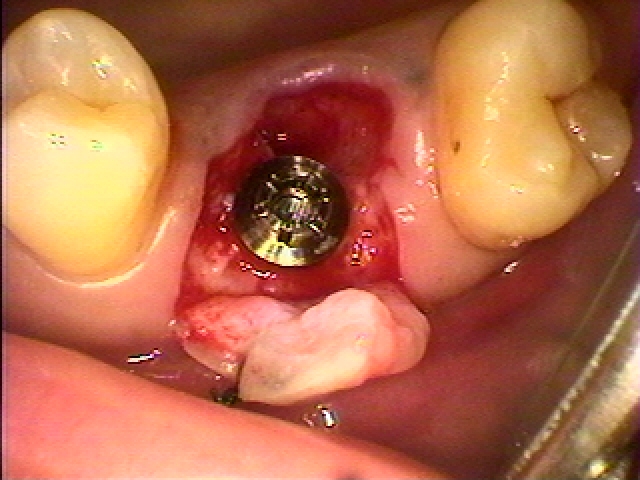

右上6番のインプラント埋入。| |広島市安佐南区の歯科医院 右上6番のインプラント埋入。 トップ お知らせ・ブログ 右上6番のインプラント埋入。 右上6番のインプラント埋入。 Web診療予約 初めての方へ 選ばれ続ける理由 院内設備について 歯が痛いしみる一般歯科 歯がぐらぐらする歯周病 健康な歯を保ちたい予防歯科 子供の虫歯予防をしたい小児歯科 銀歯をセラミックに審美歯科 白い歯を目指しませんか?ホワイトニング 矯正専門医がいるので安心矯正歯科 抜けた歯を補いたいインプラント・入れ歯 医院案内 スタッフ紹介 メリィハウス歯科クリニックオフィシャルホームページ ラベンダー歯科クリニックオフィシャルホームページ お知らせ・ブログ ホーム 診療科目 一般歯科 歯周病治療 予防治療 小児歯科 審美治療 ホワイトニング 矯正歯科 入れ歯・インプラント マウスピース矯正 初めての方へ 院長・スタッフ 設備紹介 医院案内・アクセス メニューを閉じる